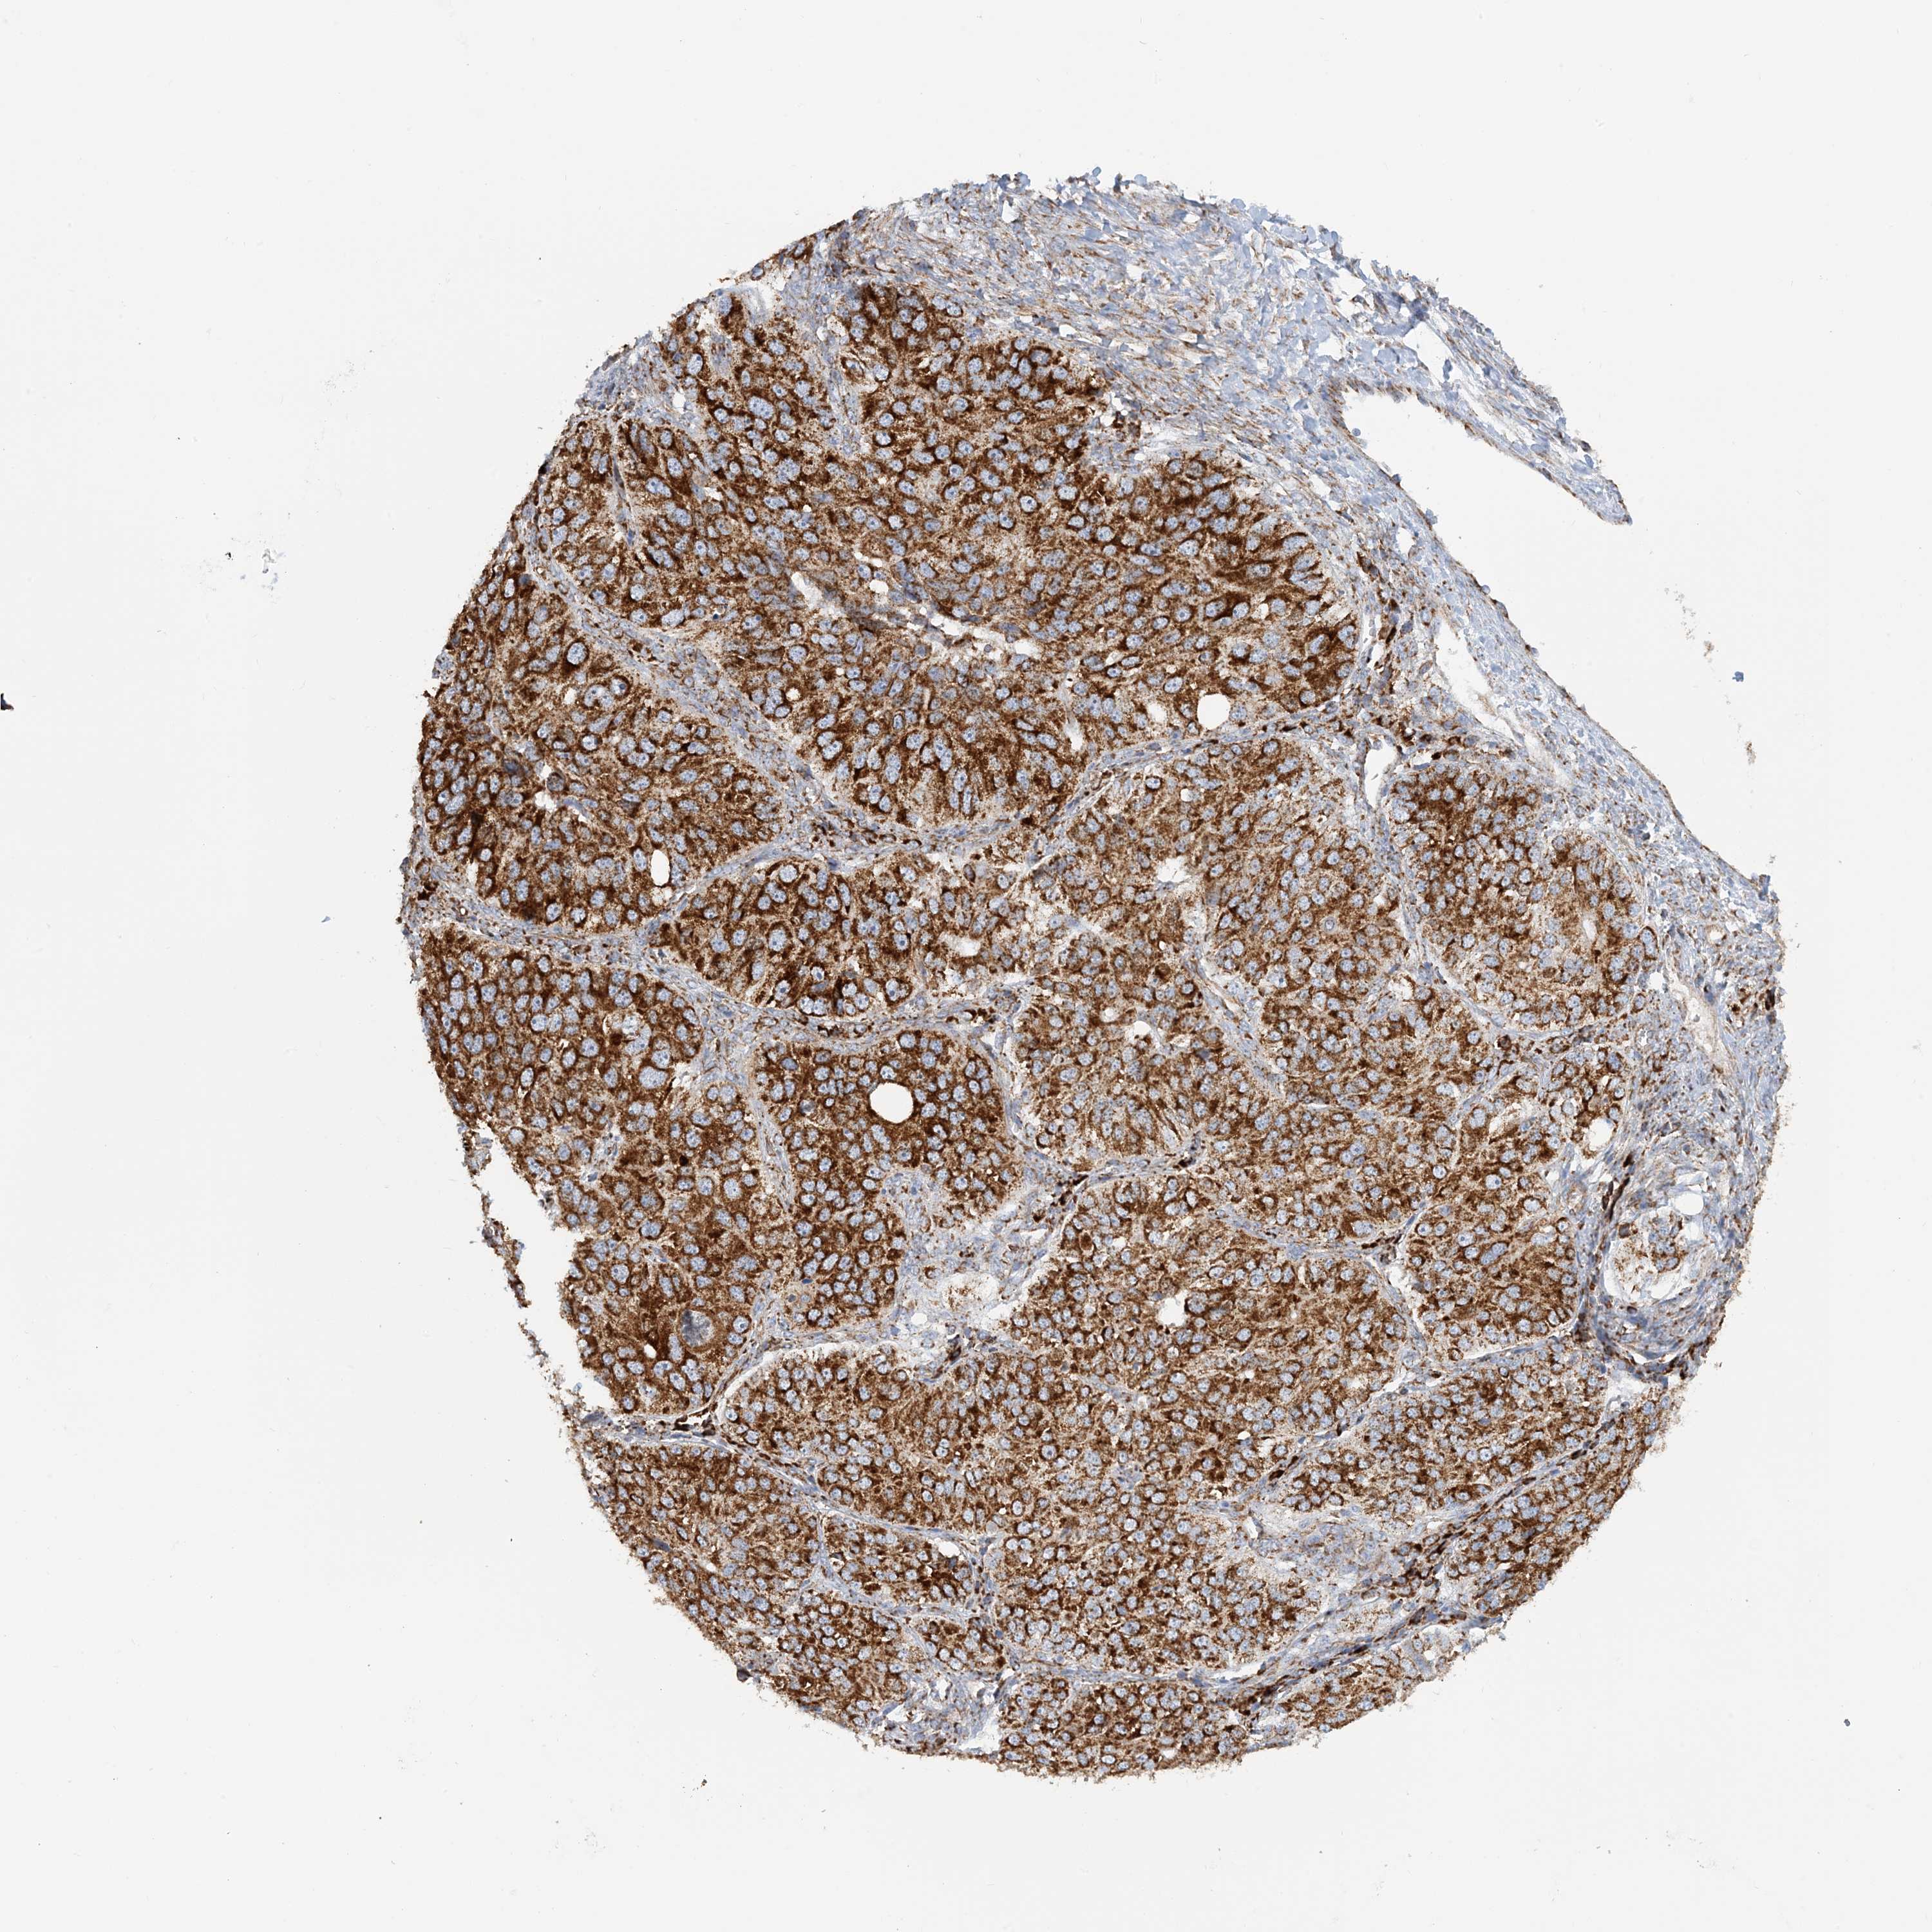

OVARIAN CANCER - Protein expressioni

A mouse-over function shows sample information and annotation data. Click on an image to view it in a full screen mode. Samples can be filtered based on level of antibody staining by selecting one or several of the following categories: high, medium, low and not detected. The assay and annotation is described here.

Note that samples used for immunohistochemistry by the Human Protein Atlas do not correspond to samples in the TCGA dataset.

Antibody stainingi

Antibody staining in the annotated cell types in the current human tissue is reported as not detected, low, medium, or high, based on conventional immunohistochemistry profiling in selected tissues. This score is based on the combination of the staining intensity and fraction of stained cells.

Each image is clickable and will lead to virtual microscopy that enables deeper exploration of all samples and also displays staining intensity scores, fraction scores and subcellular localization as well as patient and tissue information for each sample.

Antibody HPA031966

Cystadenocarcinoma, serous, NOS

Carcinoma, endometroid

Cystadenocarcinoma, mucinous, NOS

Carcinoma, NOS